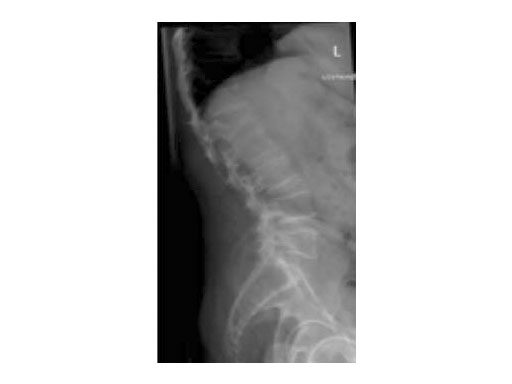

A 78-year-old woman was affected by steroid induced osteoporosis. She had persisting pain (mechanic and muscular) due to static imbalance (hyperkyphosis) and nonunion 8 months after a minor trauma with a vertebral compression fracture and vertebra plana of L1, and development of symptomatic stenosis of the spinal canal with loss of mobility over time. Pre-existing degenerative lumbar scoliosis was increased by the fracture.